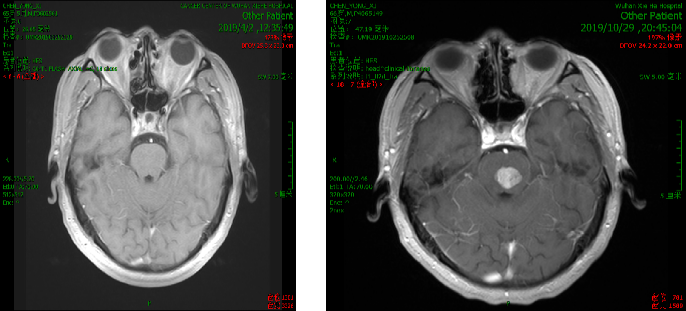

2019年10月患者出现头晕严重,不能下床独立行走,伴额头及右侧肢体麻木。

2019.10.18 当地医院头部MRI示:脑干区异常信号,约11mm*15mm,考虑转移瘤合并脑卒中。

脑部蛋氨酸PET示:脑桥结节,蛋氨酸代谢异常增高,SUVmax 4.51,考虑转移性恶性肿瘤。

影像科、神经内科会诊,考虑脑部病灶为肠癌转移病灶。

脑干转移病变,合并瘤卒中,周边水肿。

处理:2019.11.5至2019.11.10行射波刀放疗,DT 20GY/4F,同步替莫唑胺化疗。

10天后复查脑部CT提示病灶变化不明显,出血量无增加,水肿无增加。

处理:再次射波刀追加剂量,DT 20GY/4F,贝伐珠单抗200mg治疗一次。

效果:患者脸部麻木及右侧肢体麻木症状改善明显,肌力IV级,可独自行走。